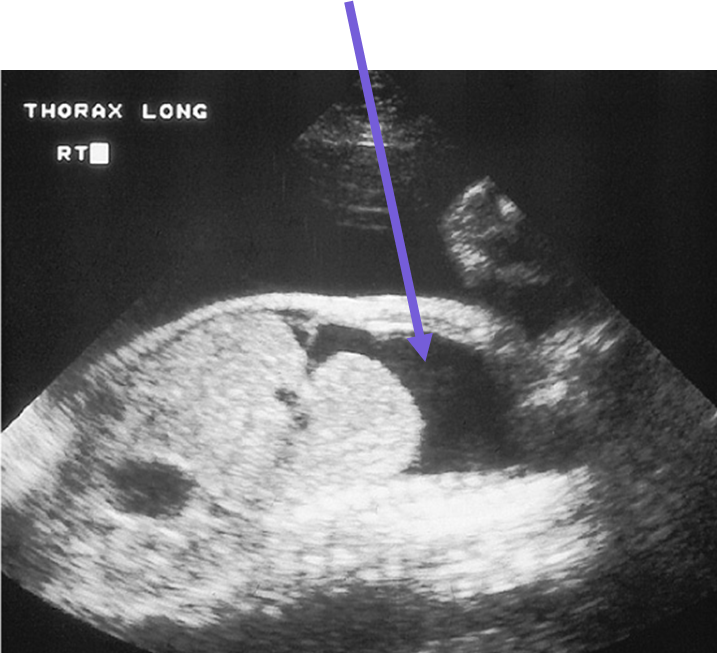

diaphragm

CDH